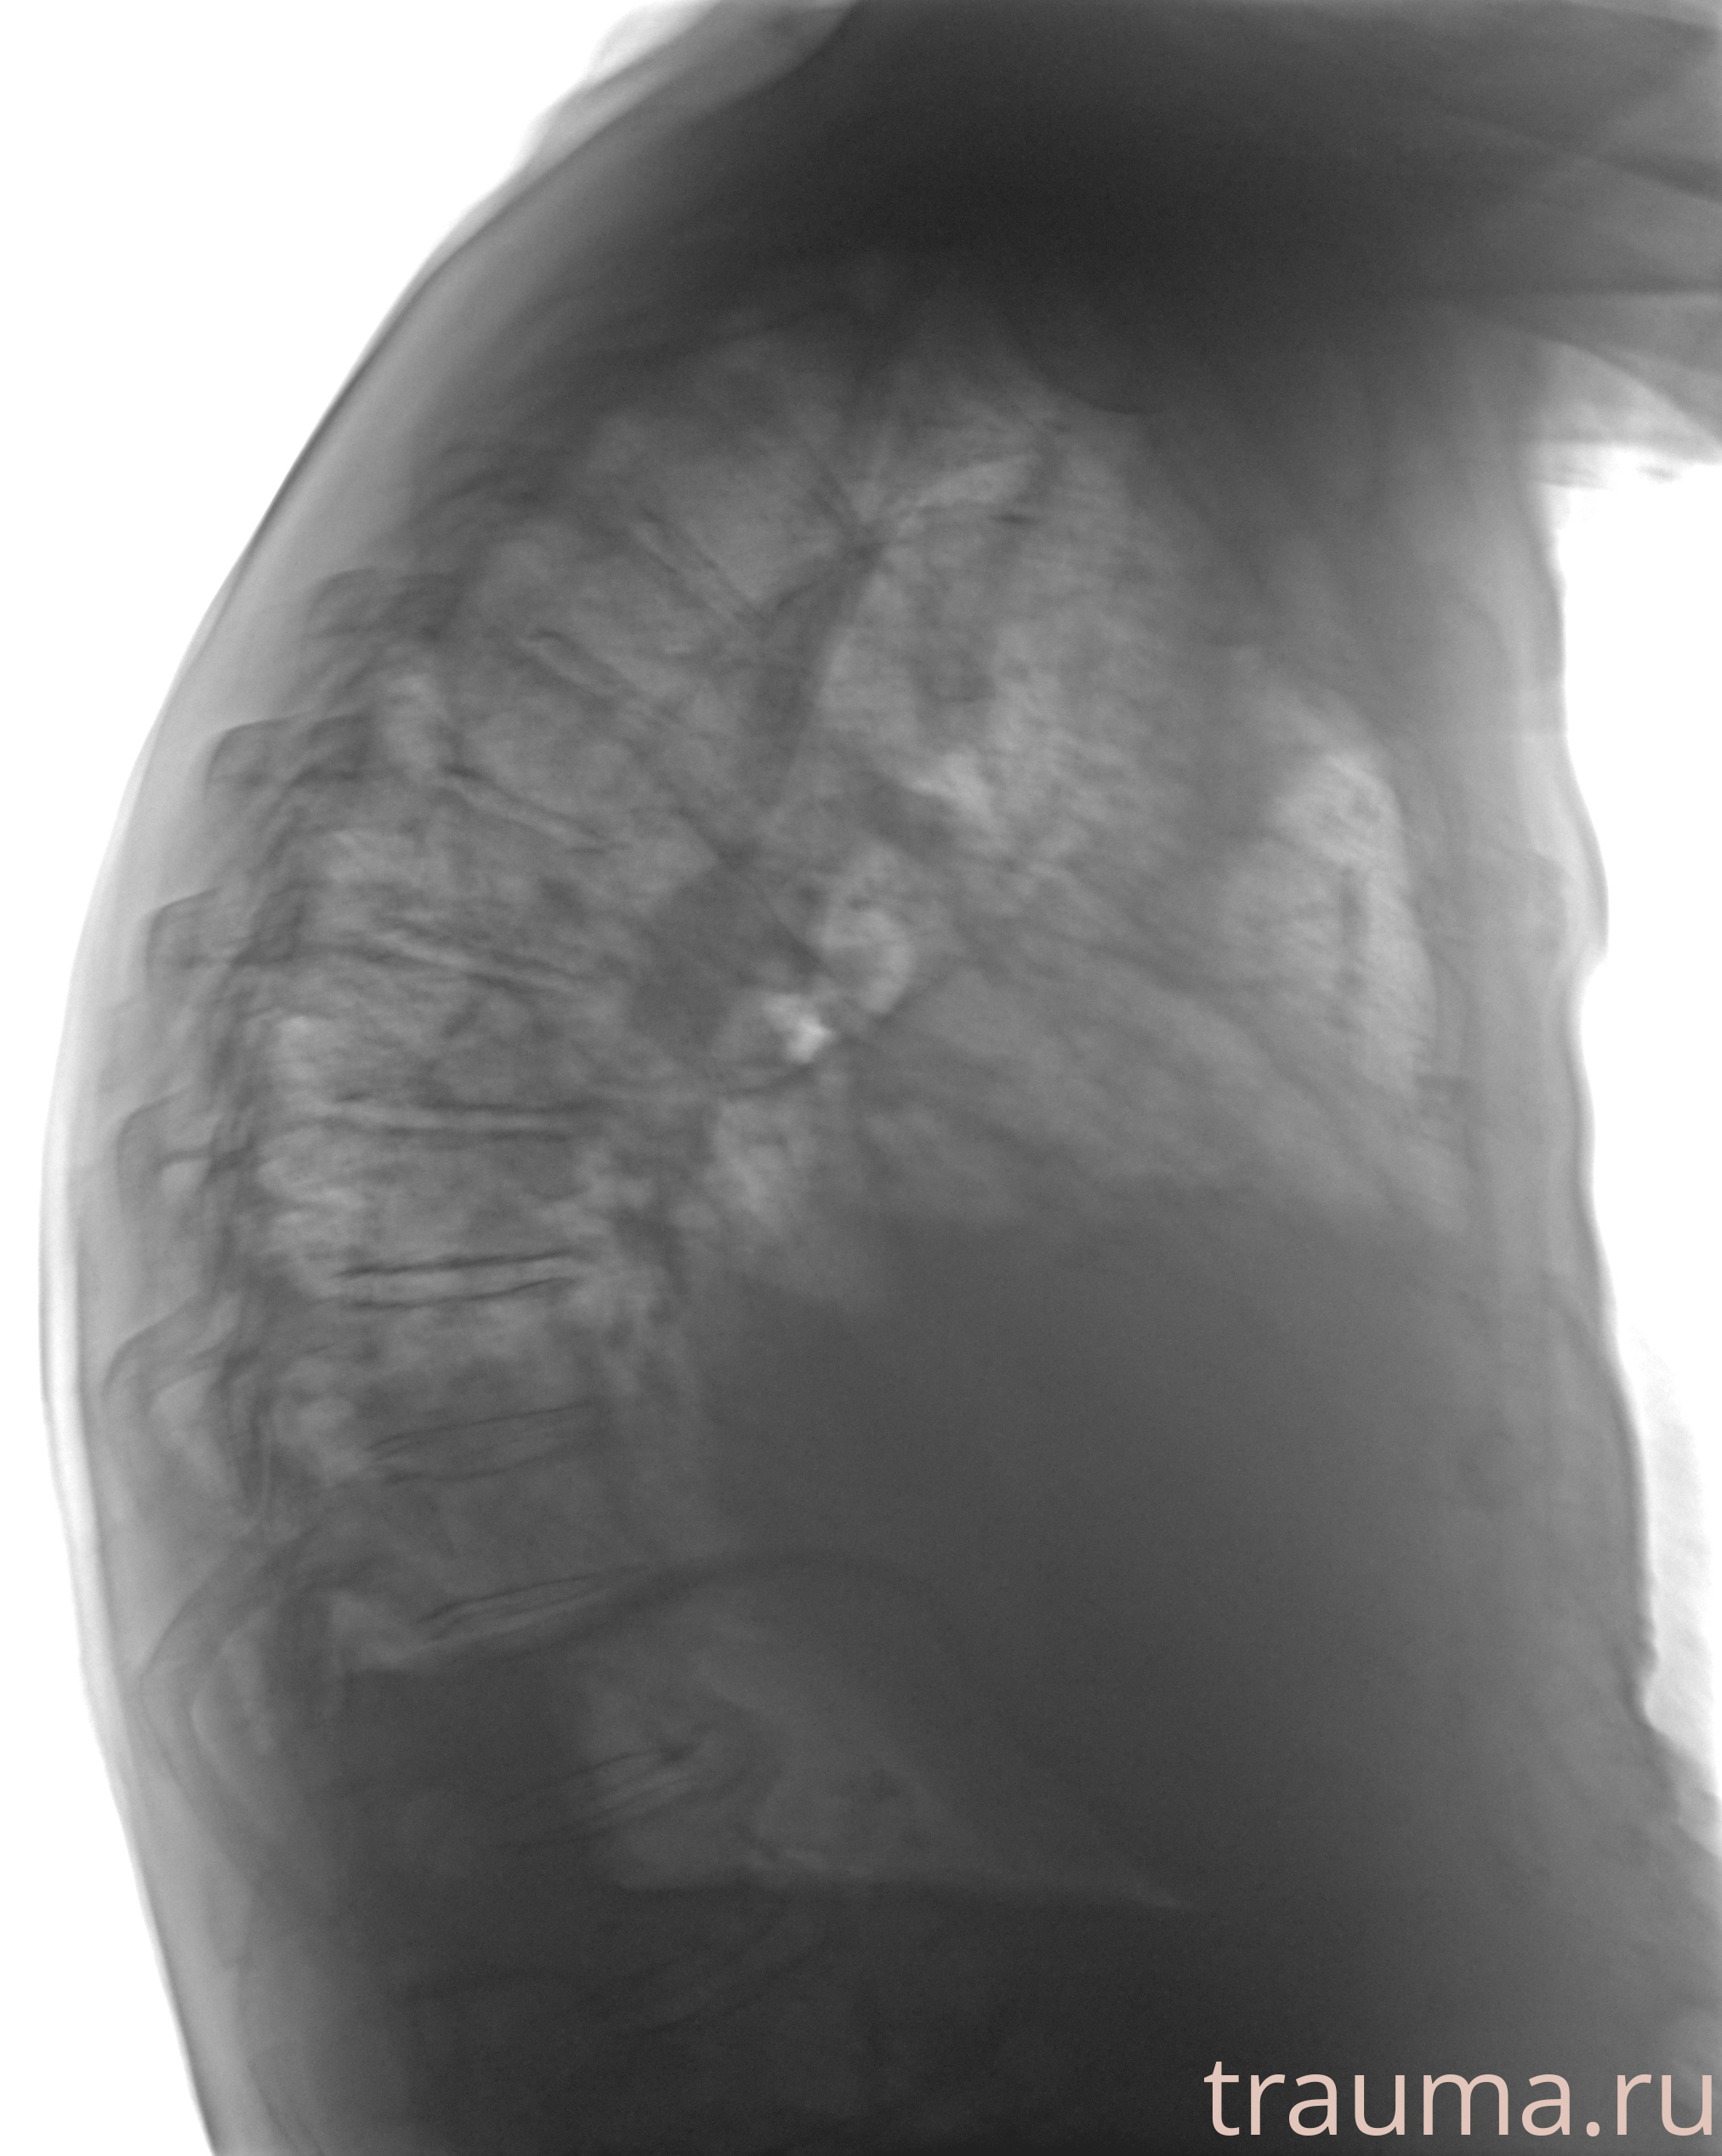

Рентген на дому: по вашему адресу приезжает врач-рентгенолог, травматолог-ортопед с мобильным рентгеновским аппаратом, проводит диагностику травмы или заболевания, делает необходимые рентгенограммы, дает рекомендации по дальнейшему лечению. Получить качественные снимки в домашних условиях возможно благодаря уникальной методике, разработанной МосРентген Центром для института  Склифосовского

при переломе шейки бедра и пневмонии от компании МосРентген Центр - партнера Института имени Склифосовского